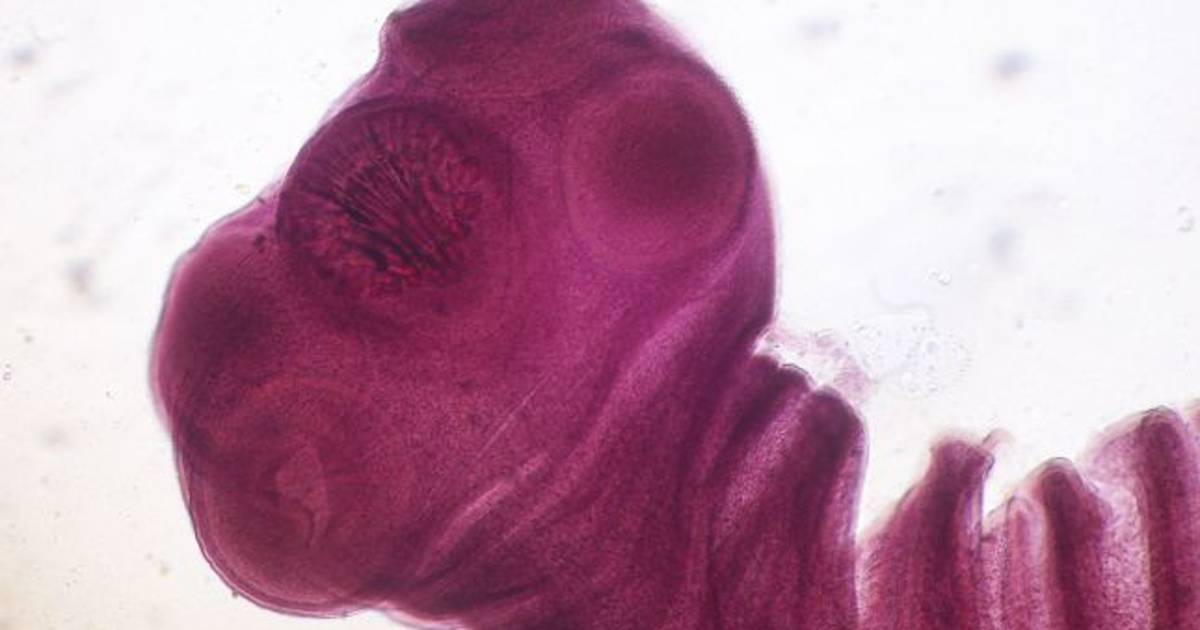

China. El Sr. Wang, un hombre chino, ha estado compartiendo durante 15 años su cerebro con una tenia, también conocida como solitaria, sin saberlo. Ahora lo han operado y le han sacado el insecto de su cabeza.

El hombre fue operado a finales de octubre, en un centro médico de la provincia de Guangdong (China). El insecto medía 12 centímetros y se estaba comiendo el tejido de su cerebro.

Según el neurocirujano que ha dirigido la operación, Gu Youming, si no se hubiera detectado el parásito en el cerebro del paciente y se le hubiera extraído, podría haber tenido graves consecuencias. La tenia se habría seguido comiendo la masa cerebral del hombre, y él se podría haber quedado paralizado o, incluso, morir.

Además, el doctor ha señalado que la intervención, que ha durado dos horas, era muy importante para sacar el insecto entero: "Si hubiera quedado alguna parte en el cerebro, habría vuelto a crecer", asegura.

Caracoles fritos, la causa

Después de la intervención, Wang ha recordado que el 2004 era aficionado a comer caracoles de río fritos con su cabeza. Un año después, en el 2005, asegura haber empezado a sentir los dolores, las náuseas, pinchazos en los brazos y las piernas y convulsiones.

El médico sospecha que el paciente se contagió con la carne del caracol, que quizás estaba poco cocida, o con algún otro animal exótico.